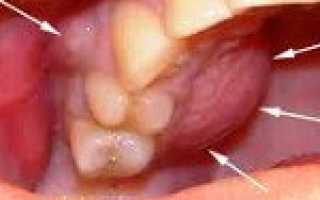

Одонтогенный периостит: фото